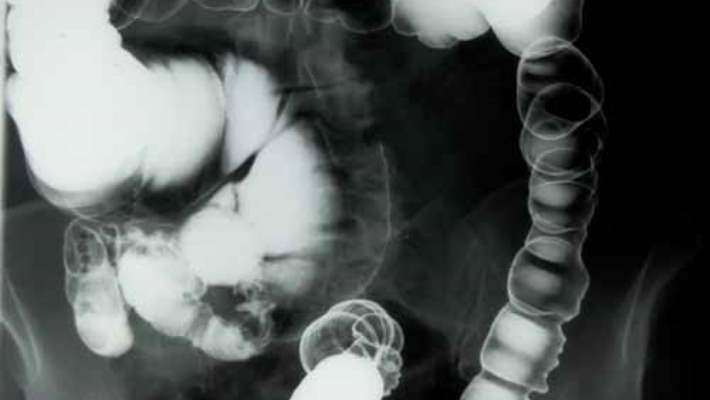

Sanal kolonoskopi kalın bağırsak (kolon) ve rektumda (kalın bağırsağın son kısmı) oluşan anormallikleri veya değişiklikleri tespit etmek için kullanılan bir işlemdir.

Sanal kolonoskopi sırasında bilgisayarlı tomografi olarak bilinen bir görüntüleme tekniğiyle karın bölgesindeki organların yüzlerce kesitsel görüntüsü üretilir. Görüntüler kolon ve rektumun içinin ayrıntılı bir görüntüsünü almak için birleştirilir ve dijital olarak düzenlenir. Konvansiyonel kolonoskopinin aksine sanal kolonoskopide sakinleştirici bir ilaç alınması veya kolona görüntüleme cihazı yerleştirilmesi gerekmez.